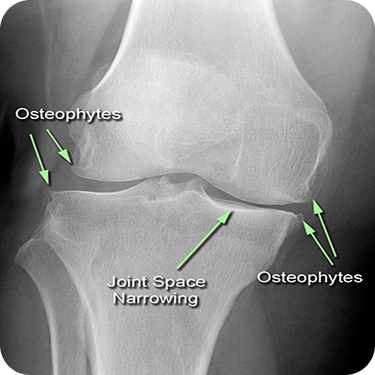

Pain from injury or repetitive movement

Degenerative joint conditions

Chronic inflammation

Wrist, ankle, or elbow pain

Hip joint stiffness

Shoulder pain or rotator cuff injuries

Knee arthritis

1. Individuals Seeking Highly Targeted Pain Relief

Those who want precise and effective reduction of joint pain.

2. People with Arthritis or Joint Degeneration

Clients suffering from chronic joint conditions requiring specialized care.

3. Those Experiencing Joint Swelling and Stiffness

Ideal for reducing inflammation and improving mobility.

4. Patients with Complex Joint Anatomy

When precision is crucial due to difficult-to-access or intricate joint structures.